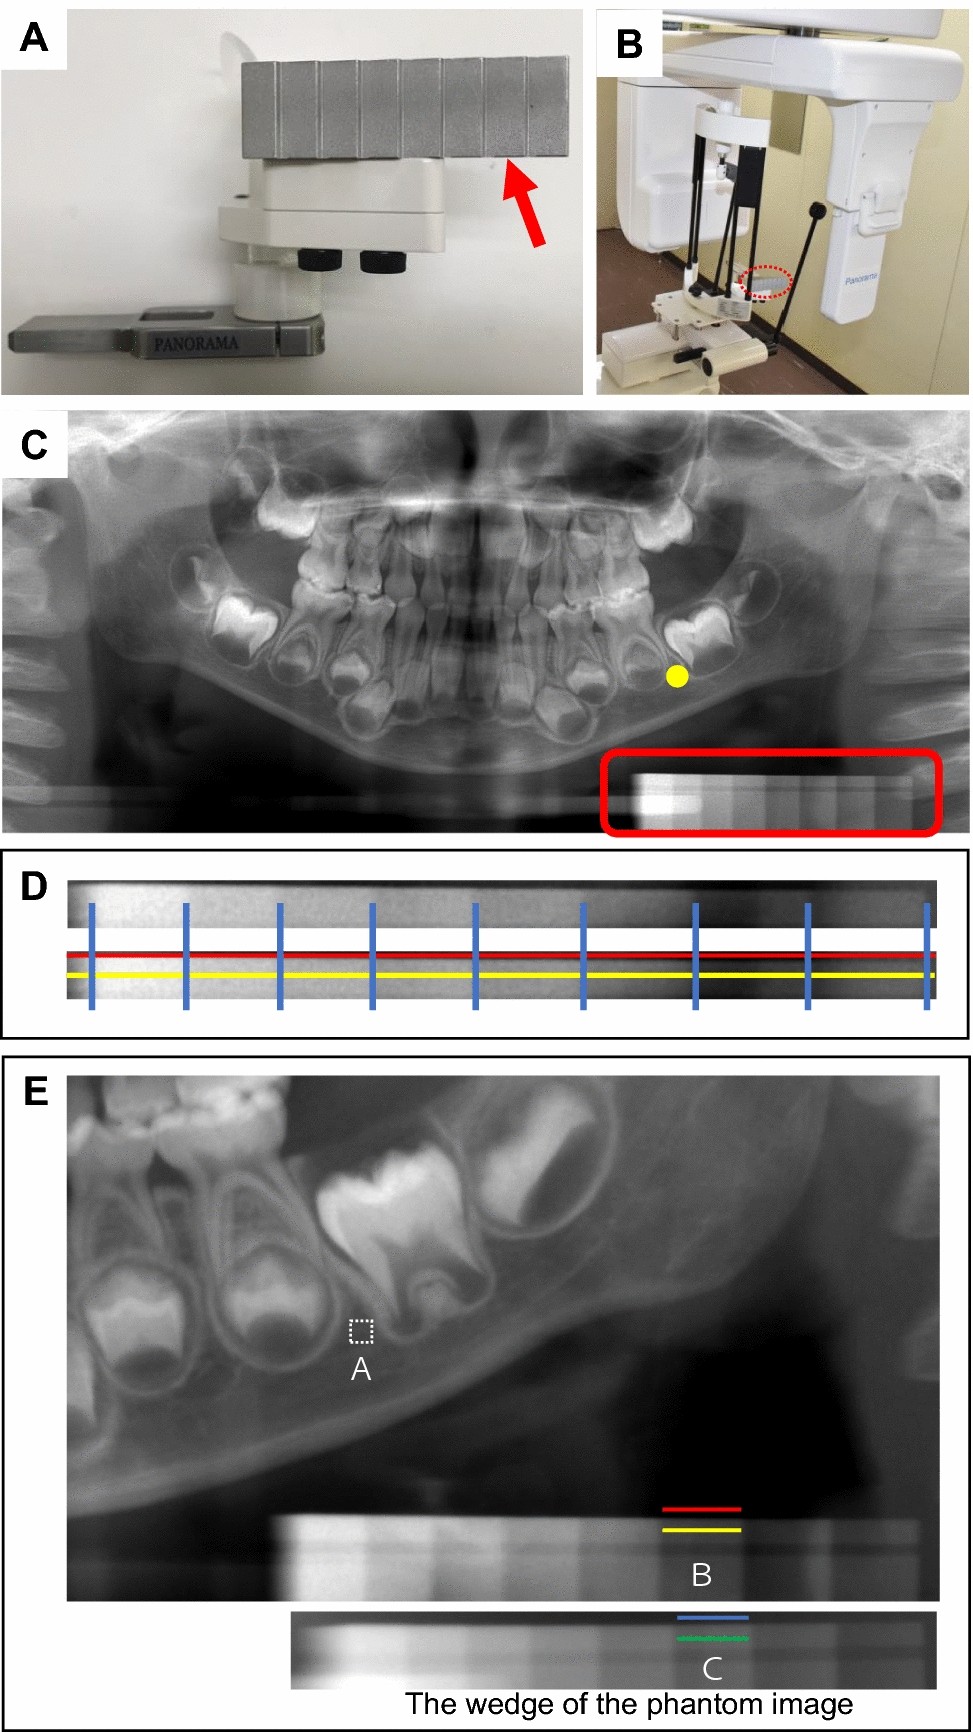

Evaluation of alveolar bone hypomineralization in pediatric ...